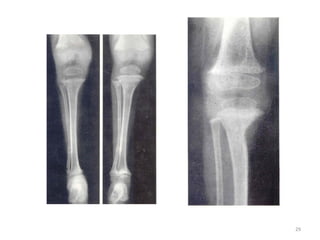

SIGNES METAPHYSAIRES

- Elargissement des bases métaphysaires avec aspect en cupule ou « toit de

pagode »

- Elargissement des zones radio-transparentes (points d’ossification)

ATTEINTES EPIPHYSAIRES

- Retard d’apparition des points d’ossification

- Points d’ossification flous ou irréguliers

LESIONS DIAPHYSAIRES

- Diminution de la densité osseuse

- Amincissement des corticales

- Aspect de corticale feuilletée

- Coxa vara, genu varum

- Pseudo-fracture de Looser- Milkmann